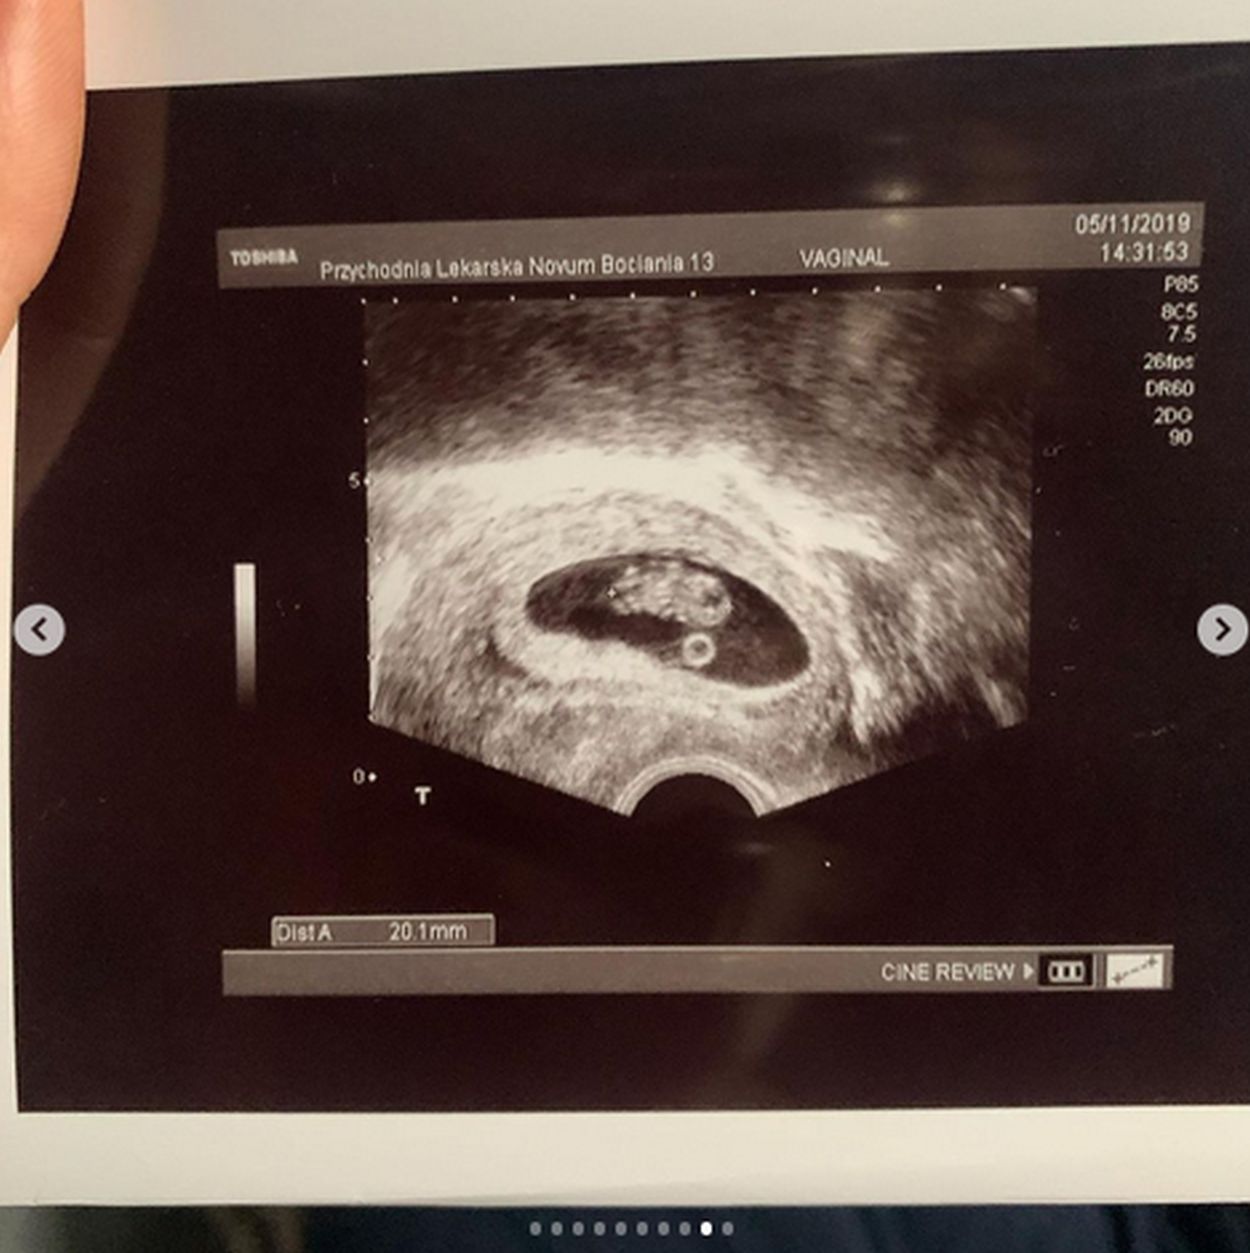

Małgorzata Rozenek z okazji urodzin pociechy pokusiła się również o pokazanie fotografii wykonanych chwilę po tym, jak dowiedziała się, że jest w ciąży. Fajna pamiątka dla Henia?

(...) Dzięki wspaniałej opiece i ogromnej wiedzy, po pewnych perturbacjach - STAŁO SIĘ! - pisze rozemocjonowana celebrytka, następnie zwracając się bezpośrednio do lekarzy, pod których okiem przez lata próbowała zajść w ciążę: Do końca życia będziemy wdzięczni (...) - czytamy pod szeregiem niepublikowanych wcześniej szpitalnych zdjęć 43-latki.

W dodanym godzinę później wpisie "Perfekcyjna" opisuje chwile po tym, jak dowiedziała się, że zostanie mamą.

O ciąży dowiedziałam się na pięć minut przed wejściem do samolotu. Później biegałam po Londynie w euforii - wspomina pod fotografiami wykonanymi w tamtym czasie i zdjęciem testu ciążowego z czworonogami w tle: